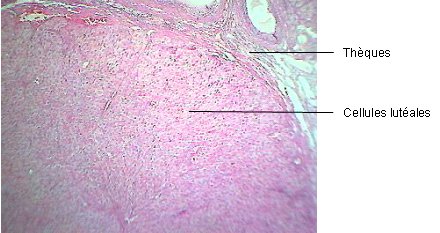

Du 1er au 14ème jour du cycle, le follicule subit une croissance et une maturation (follicule mûr ou de De Graaf) qui le conduiront à expulser l'ovocyte au 14ème jour du cycle : c'est l'ovulation. Le gamète femelle sera alors recueilli par les trompes de Fallope. Il pourra éventuellement être fécondé par un spermatozoïde, donnant alors naissance à une cellule-œuf puis, après divisions cellulaires, à un embryon. La structure folliculaire restante dans l'ovaire évoluera en corps jaune : les cellules de la granulosa se multiplient et se différencient en cellules produisant un pigment jaune, les cellules lutéales. En l'absence de fécondation, le corps jaune régressera 14 jours après l'ovulation.

Les photos ci-dessous représentent l'aspect des follicules ovariens à des stades différents du cycle.

Corps jaune (x 40)